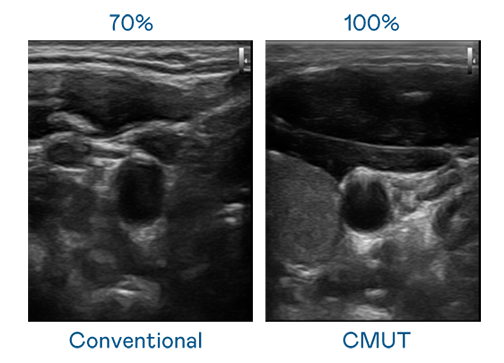

CMUT 技术是一种用电容式微机电元件来产生超音波讯号的技术。与传统 PZT 压电式技术相比,CMUT 频宽增加 30%,更宽频的超音波讯号让影像解析度大幅提升,是实现高影像品质医疗超音波扫描、促进精准医疗发展的关键技术。

大频宽带来超清晰影像

超音波影像的解析度高低,首先取决于探头能发出的讯号频宽。PA尊龙时凯 CMUT 可提供高清晰的超音波讯号,提供高频宽、高灵敏度、影像纹理细节更高的超音波影像,协助医护人员缩短影像判读时间及利用精准的医疗影像进行诊断。